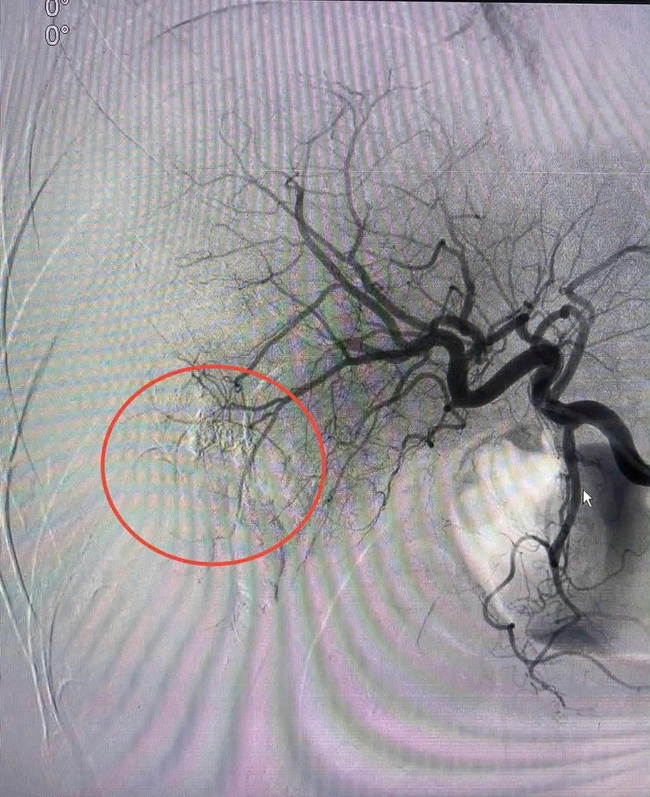

Bác sĩ Nguyễn Đức Hùng- Trưởng khoa Chẩn đoán hình ảnh và Điện quang can thiệp, người trực tiếp thực hiện ca can thiệp, cùng ekip đã tiến hành luồn vi ống thông từ động mạch đùi đến vị trí động mạch gan đang chảy máu. Dưới màn hình tăng sáng, các bác sĩ đã bơm vật liệu gây tắc mạch để bít hoàn toàn điểm vỡ.

Chỉ sau 20 phút vừa hồi sức tích cực vừa can thiệp, vị trí chảy máu đã được kiểm soát hoàn toàn. Huyết áp của bệnh nhân dần trở lại bình thường, các chỉ số sinh tồn ổn định, chính thức thoát khỏi tình trạng sốc nguy kịch.

Vị trí chảy máu đã được can thiệp bít điểm vỡ.